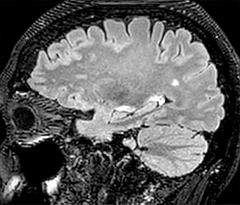

A two year follow-up scan of a CPA meningioma using both Ingenia 3.0T without CS and Ingenia Elition 3.0T with Compressed SENSE allows for a nice comparison to demonstrate the protocol improvements achieved on the Elition: 3D FLAIR has a shortened scan time, improved SNR and still the same spatial resolution. BrainView (3D T1 TSE) has improved spatial resolution and SNR with shortened scan time. For 3D T2 Drive the spatial resolution has been improved. 3D THRIVE used to have an interpolated 0.8 mm slice thickness, but true thickness at 1.6 mm, so that axial slices displayed a decent quality, but reformats were suboptimal.

Compressed SENSE is used on Elition to improve spatial resolution and reduce the non-interpolated slice thickness to allow smoothly reformatted images. Total scan time (adding SmartBrain and an additional b2000 diffusion) was 13:19 on Ingenia, and is now reduced to 10:42 on Ingenia Elition.

Ingenia 3.0T (without Compressed SENSE)

3D FLAIR (without Compressed SENSE)

3D FLAIR

1.0 x 1.0 x 1.0 mm*

4:24 min.

3D TSE T1w (without Compressed SENSE)

3D TSE T1w

1.0 x 1.0 x 1.2 mm*

2:40 min.

3D T2w Drive (without Compressed SENSE)

3D T2w Drive

0.8 x 0.8 x 1.0 mm*

3:05 min.

3D T1w THRIVE (without Compressed SENSE)

3D T1w THRIVE

0.8 x 0.8 x 1.6 mm*

1:30 min.

Ingenia Elition 3.0T with Compressed SENSE

3D FLAIR (with Compressed SENSE)

2:50 min.

3D TSE T1w (with Compressed SENSE)

2:10 min.

3D T2w Drive (with Compressed SENSE)

0.7 x 0.7 x 0.7 mm*

2:52 min.

3D T1w THRIVE (with Compressed SENSE)

0.7 x 0.7 x 0.8 mm*

*true voxel size, without interpolation